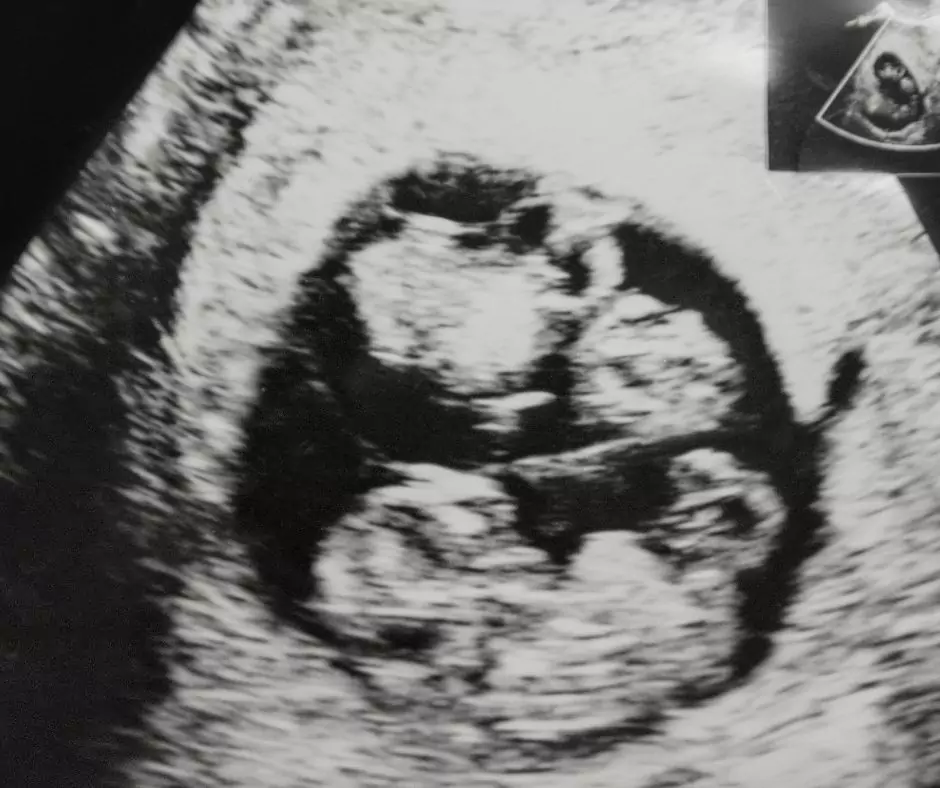

• Badanie USG: to podstawowy i najdokładniejszy sposób potwierdzania bliźniąt, umożliwiający wizualne potwierdzenie dwóch płodów i ich rozwoju.

Najdokładniej potwierdza ją badanie USG, które pozwala zobaczyć dwa płody i ocenić ich rozwój. Pomocniczo lekarz może wykorzystywać badanie kliniczne, badania krwi (np. hCG) oraz monitorowanie tętna płodów (np. doppler) w trakcie opieki prenatalnej.